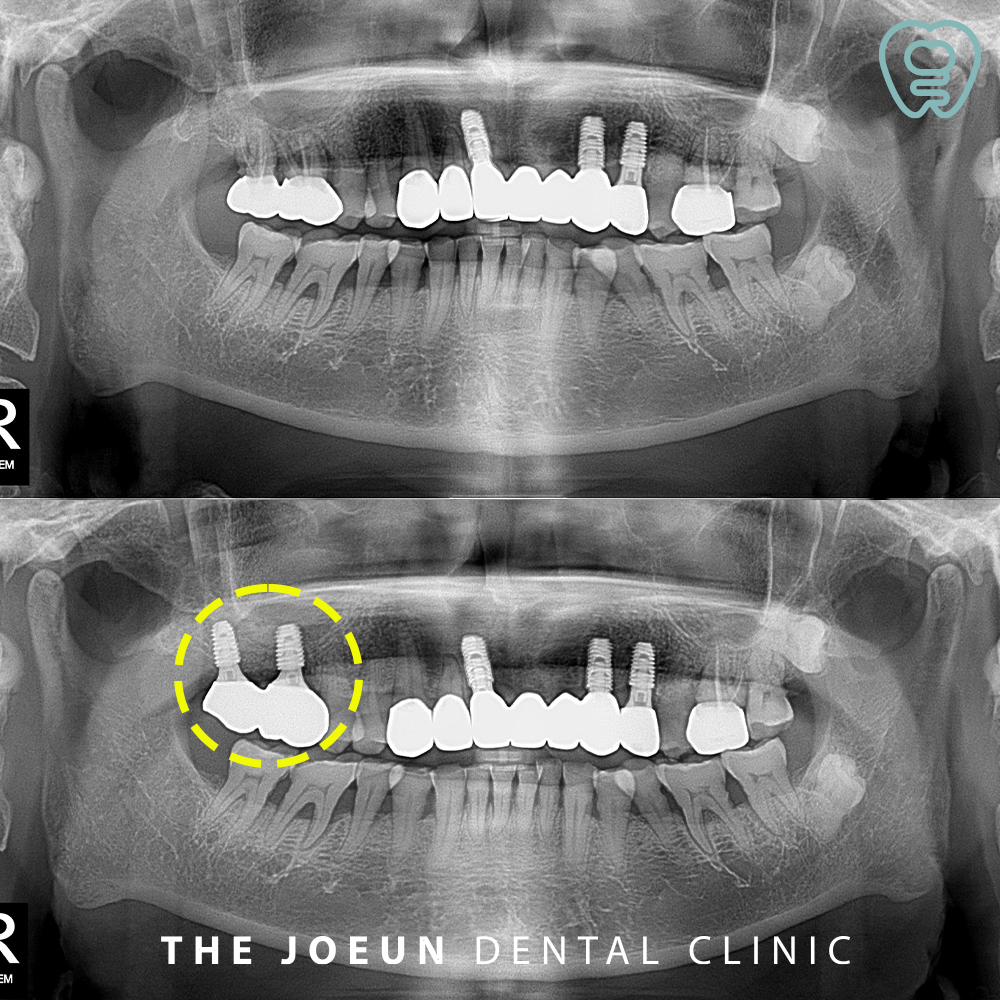

임플란트 식립 후 뼈와 단단하게 융합될 수 있는 약 3개월의 시간을 더 기다려 준 뒤 최종 보철물을 진행하였는데요.

상악동거상술 이후에는 일정 기간 동안 붓기나 코막힘 등의 증상이 일시적으로 나타날 수 있고 비강과 인접한 부위인 만큼 과도한 압력이 전달되는 행동은 피해야 하며, 특히 코를 세게 푸는 행동이나 심한 운동, 비행기 탑승 등은 제한되는 경우가 있어 일반적으로 1~2주 내 증상은 완화되며 이후 일정한 기간 동안 골 재생 상태를 관찰하여 안정적인 상태를 확인한 후 보철을 진행하여야 합니다.

시술 방식의 선택은 환자의 상악동 형태, 골의 높이, 전신 건강 상태 등을 종합적으로 판단해 결정되며 난이도가 높은 기술이 요구되는 만큼 임상 경험이 풍부한 강창역치과 의료진과의 상담과 집도가 중요합니다. 또한 3D CT를 활용한 정밀 진단을 통해 상악동 내 염증이나 병변 유무, 해부학적 구조를 사전에 파악하는 과정도 반드시 선행되어야 합니다.